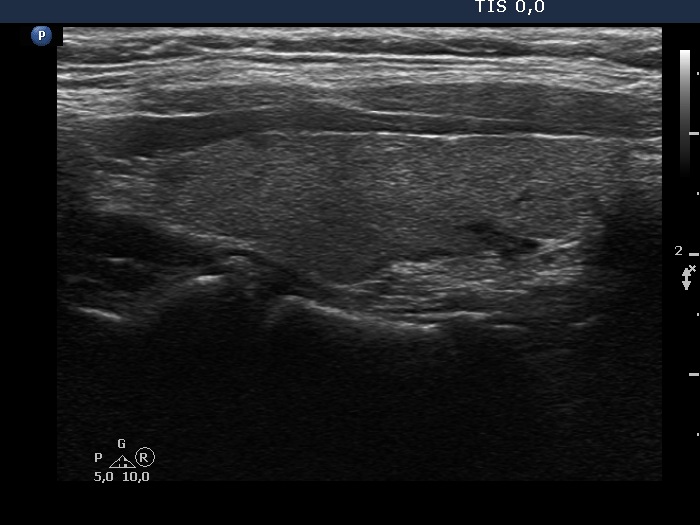

Ultrasonography. The thyroid was echonormal. There were two nodules in the left lobe. The upper lesion was a dominantly isoechoic nodule which had microcalcifications while the lower one was a hypoechoic nodule. There were numerous microcalcification relatively far from the primary tumor focus. The upper nodule was avascular while the lower one presented both intranodular and perinodular blood flow.